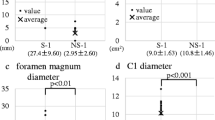

While hydrocephalus at birth type showed significantly larger ICV than the others, there were no statistical differences between no hydrocephalus and progressive hydrocephalus (Fig. 3a). In LVV, even progressive hydrocephalus showed a significantly larger volume than no hydrocephalus (Fig. 3b). In CPV, both progressive hydrocephalus and hydrocephalus at birth demonstrated significantly larger volumes than no hydrocephalus; however, there was no statistical difference between these two types (Fig. 3c). Conversely, PCFV in no hydrocephalus exhibited significantly larger values than those in other two types (Fig. 3d). According to MMC lesion vertebrae count, hydrocephalus at birth demonstrated significantly larger values than no hydrocephalus (Fig. 3e). For exact values, refer to Supplemental Table 1.

Differences among three hydrocephalus types. The box-and-whisker plot overlaid with beeswarm plots is presented for intracranial volume (ICV) (a), lateral ventricles volume (LVV) (b), choroid plexus volume (CPV) (c), posterior cranial fossa volume (PCFV) (d), and Myelomeningocele (MMC) lesion vertebrae count (e). The Wilcoxon rank-sum test is used, and acquired p-values are corrected by Bonferroni correction, multiplied by three, for the solution of multiple comparisons. Statistically significant corrected-p values < 0.05 are denoted with an asterisk. Hydrocephalus types are presented as 0 for no hydrocephalus, 1 for progressive hydrocephalus, and 2 for hydrocephalus at birth